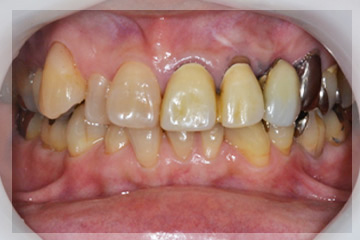

初診時

| 年齢・性別 | 50代・女性 |

| 主訴 | 顎が痛い、疲れる。 |

| 治療期間 | 約3年 |

| 費用 | 総額:130万円+保険費用 |